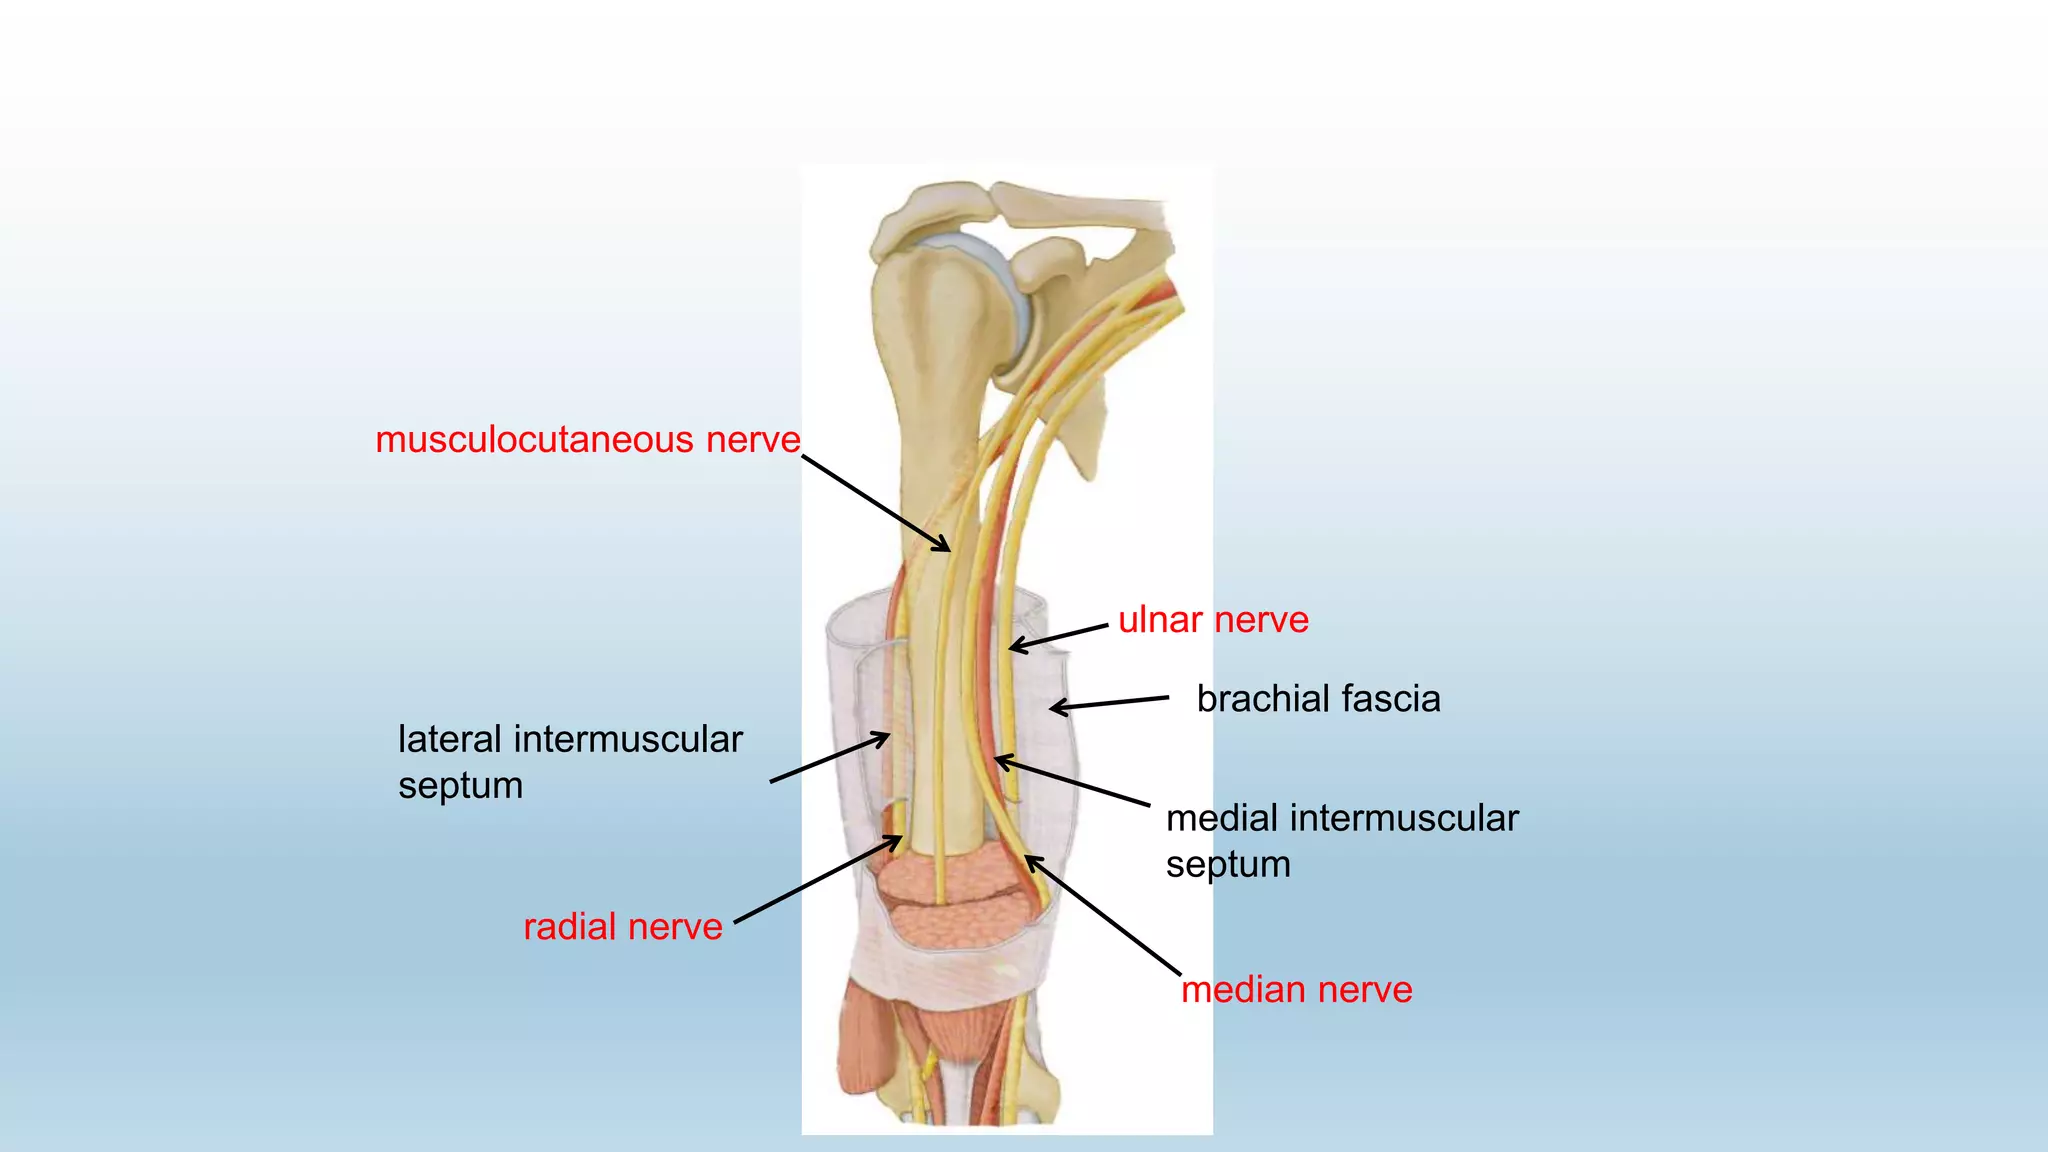

The document summarizes an anatomy revision session on the upper limb. It discusses various muscles of the upper limb including their origins, insertions, innervations and functions. Key muscles covered include the pectoralis major and minor, serratus anterior, deltoid, biceps brachii, brachialis, coracobrachialis, and triceps. It also discusses the rotator cuff muscles and muscles of the forearm including flexor carpi ulnaris and radialis. The session aims to help students identify upper limb muscles and understand their relations to nerves.